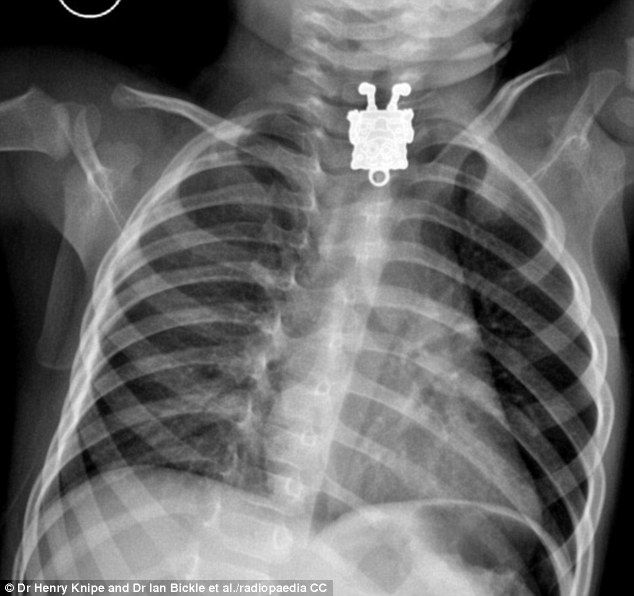

異物を飲み込んだ乳児をレントゲンしたら「スポンジボブ」が映ったと話題に|面白ニュース 秒刊SUNDAY

1歳4ヶ月の子供がペンダントを飲んでしまった

急いで病院に連れて行きレントゲン写真をとってみると・・・

> スポンジボブ <

もちろんこの乳児から異物は取り出され、無事退院した